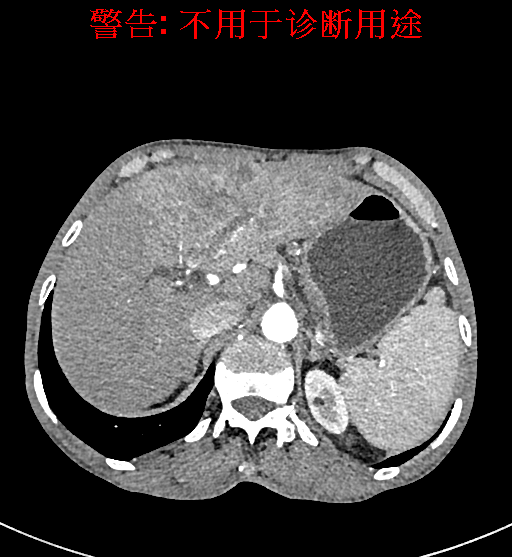

实验室检查: 血常规:WBC 4.89*109/L,RBC 3.64*1012/L, HB 119.00g/L, HCT 35.40%,PLT 123*109/L,RET% 0.48%, RET 0.017*1012/L, IRF 2.00%生化全套:ALT 56.00U/L AST 60.00U/L, LDH 312.00U/L TP 72.08g/L ALB 32.44g/L, GGT 101.00U/L,TBA 21.90umol/L,A/G 0.82,ADA 23.00U/L, PAB 94.20mg/L, CHE 5405.00U/L 肿瘤标志物:CEA 2.80ng/mL CA19-9 11.46U/ml 肝炎全套: HAV-IgM 0.21S/CO, HBcIgM 0.330S/CO, HCV-cAg 0.08S/CO, HEV-IgM 0.03S/CO, HBeAg 6.000S/CO 诊疗过程: CT结果输入海信CAS系统后行3D重建及手术规划后,于2018-5-17局麻下行“经皮肝动脉造影术+肝动脉化疗栓塞术”手术治疗 术前三维重建及手术方案设计: 将0.625mm双源薄层CT资料的静脉期和动脉期Dicom格式文件导入海信CAS系统。 通过调节窗宽窗位调整CT序号,对肿瘤,肝实质,胆囊,下腔静脉,肿瘤,肝动脉、门静脉及肝静脉等进行三维重建;系统自动计算肿瘤体积和肝脏体积。肝脏体积为1563ml,肿瘤体积为537.6ml,通过比对50-60岁正常肝脏体积为1343.28±246.69ml。 手术步骤: 常规准备后,患者仰卧于DSA手术床。常规双侧股动脉区域消毒,铺巾。2%利多卡因局部麻醉右侧股动脉区成功后,应用Seldinger技术穿刺右侧股动脉,置入5F动脉鞘。送5F 肝导管至腹腔干、肝动脉造影,肝区可见团块状及多发结节状肿瘤染色、侵犯门静脉左支。静脉推注维瑞特5mg后,透视下将微导管分别超选择至各支肿瘤供血动脉内,应用雷替曲塞4mg+奥沙利铂50mg+表柔比星20mg +LP 10ml的混合液及适量350-560um明胶海绵进行栓塞,后造影示栓塞适量,退出导管、血管鞘,局部压迫10min,加压包扎。患者术中未诉不适,术后平车安返病房。随访情况: 患者术后3月复查上腹CT示肝左叶病变活性残留,腹腔内、腹膜后多发略大淋巴结,部分较前略减小,今患者为求进一步诊治,与我院再次行“肝动脉造影+经导管肝动脉栓塞术”,术后2周无明显不适 术前CT检查:动脉期

静脉期